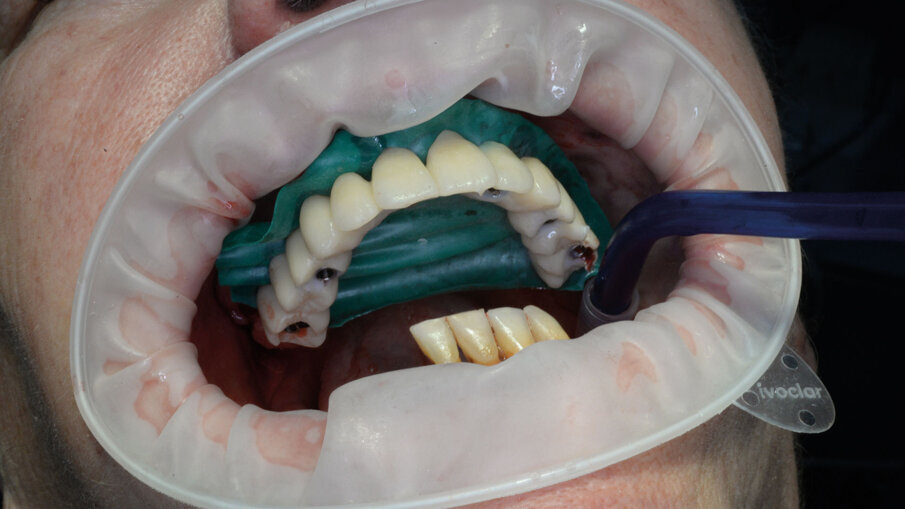

Alla preparazione dei tunnel implantari è seguito il loro inserimento sempre con tecnica guidata utilizzando gli appositi montatori forniti nel kit, avendo cura di far combaciare le tacche di riferimento dei montatori con le linee di repere preventivamente disegnate sulla dima così da ottenere il corretto posizionamento dei 2 mua angolati previsti nel settore anteriore (Fig. 14). In fase chirurgica il posizionamento dei mua è stato ulteriormente facilitato dalla presenza di un doppio esagono presente all’interno dell’impianto che rende possibili ulteriori aggiustamenti “di fino” del componente protesico. Avvitate tutte le torrette il provvisorio è stato poi cementato con cemento duale dedicato utilizzando un foglietto di diga preforato per facilitarne la cementazione (Figg. 15, 16).

Lo scambio di informazioni tramite file STL ha permesso di trasferire al laboratorio preziose informazioni sulle emergenze dei componenti protesici scelti e sulla loro relazione con i tessuti prima dell’intervento. Sulla base di queste informazioni, il laboratorio ha potuto costruire un provvisorio da cementare sulle torrette alla fine dell’intervento, simulando virtualmente il profilo dei tessuti molli dopo le estrazioni (Figg. 17-19).